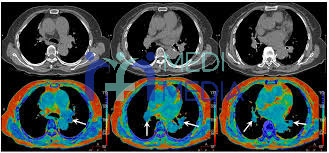

تشخیص امبولی ریوی

از جمله راه های تشخیص آمبولی ریوی عبارت اند از:

آنژیوگرام و اسکن ریوی